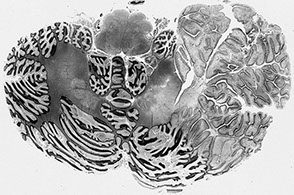

Cerebellum

From out to in, the cerebellum is made of the molecular layer, the Purkinje cell layer, a granular cell layer and an inner tract of white matter

- Purkinje cells are large neurons that get info from the granular layer and send it out into the

- Bergman glia also live im the Purkinje cells layer

- glomeruli are little pink structures found in the granular layer

Cerebellum - Molucular layer

Granular cell layer

<-- Purkinje cell

White matter

M

P

G

W